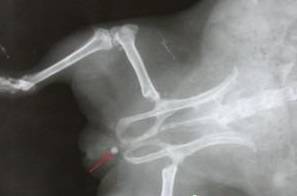

Камень в уретре самца морской свинки (отмечен красной стрелкой)

Требуется сделать рентген, камень может перекрыть уретру, тогда гибель зверька неизбежна.

Диагностика проводится комплексно. Проводят рентгенографию в 2 проекциях, это обнаруживает крупные камни и песок, но не мельчайший осадок.